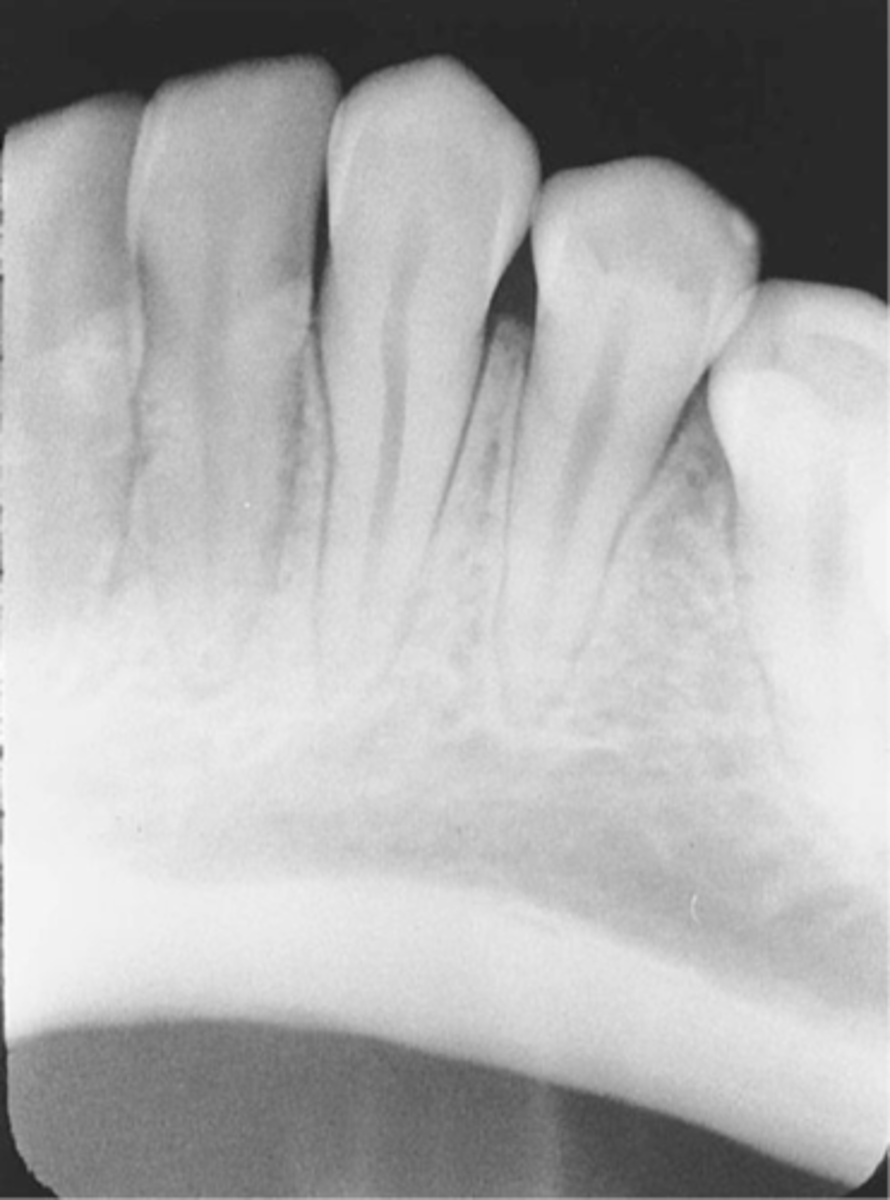

Phalangioma

-Image of the patient's finger is seen

-Error occurs when the finger-holding method is used with the bisecting technique and is not recommended

-To avoid make certain that the patient's finger used to stabilize the receptor is placed behind the receptor and not in front of it